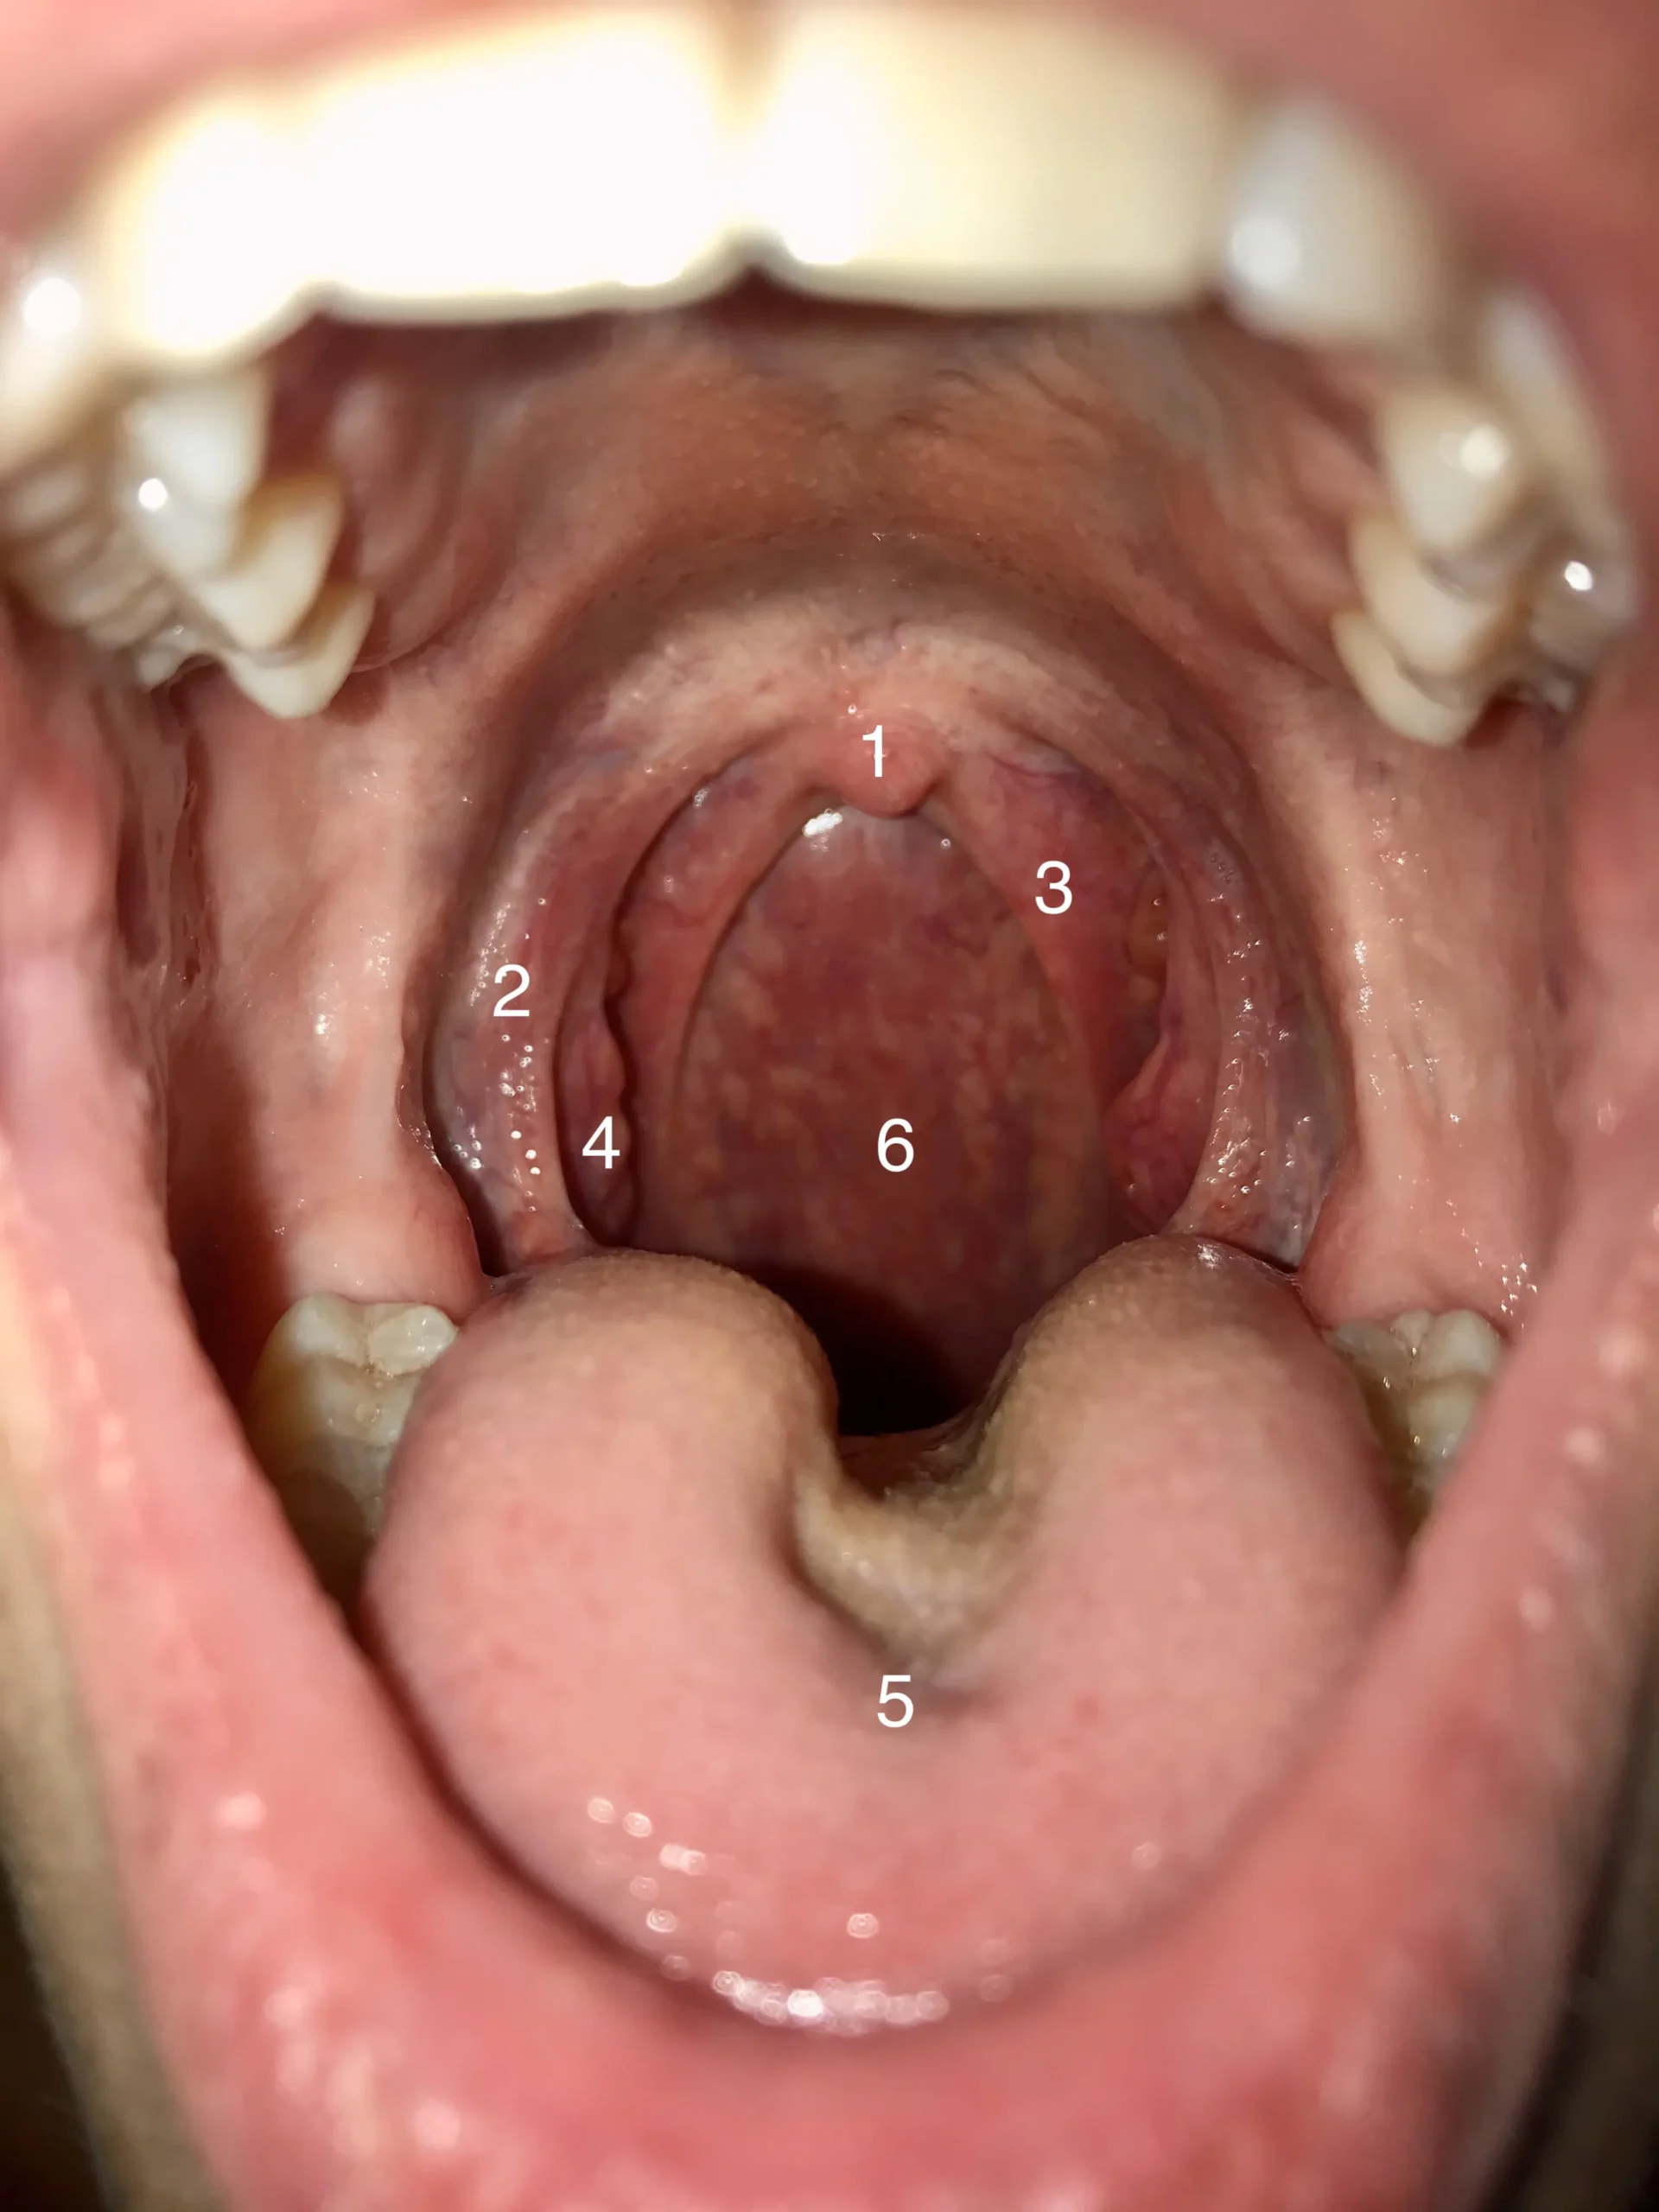

Tonsillektomie: Vollständige Entfernung der Mandeln

Bei einer Tonsillektomie werden die beiden Gaumenmandeln mit Hilfe chirurgischer Instrumente aus ihrem Bett geschält. Die Operation wird in der Regel unter kurzer Vollnarkose ambulant oder stationär durchgeführt. Eine Tonsillektomie ist ein Routineeingriff im HNO-Bereich und insgesamt eine der am meisten durchgeführten Operationen überhaupt.

Tonsillotomie: Teilentfernung der Mandeln

Eine Tonsillotomie ist eine Operation, bei der nur ein Teil der Mandeln entfernt wird. Diese Operation wird vor allem bei Kindern zwischen dem und Lebensjahr durchgeführt, wenn die Mandeln wegen ihrer abnormen Größe zu Atem- und Schluckbeschwerden führen, aber kein chronischer Entzündungsherd sind. Bei einer Tonsillotomie wird ein Teil der Gaumenmandeln ambulant (z.B. Per Laser oder mittels Radiofrequenz) abgetragen.